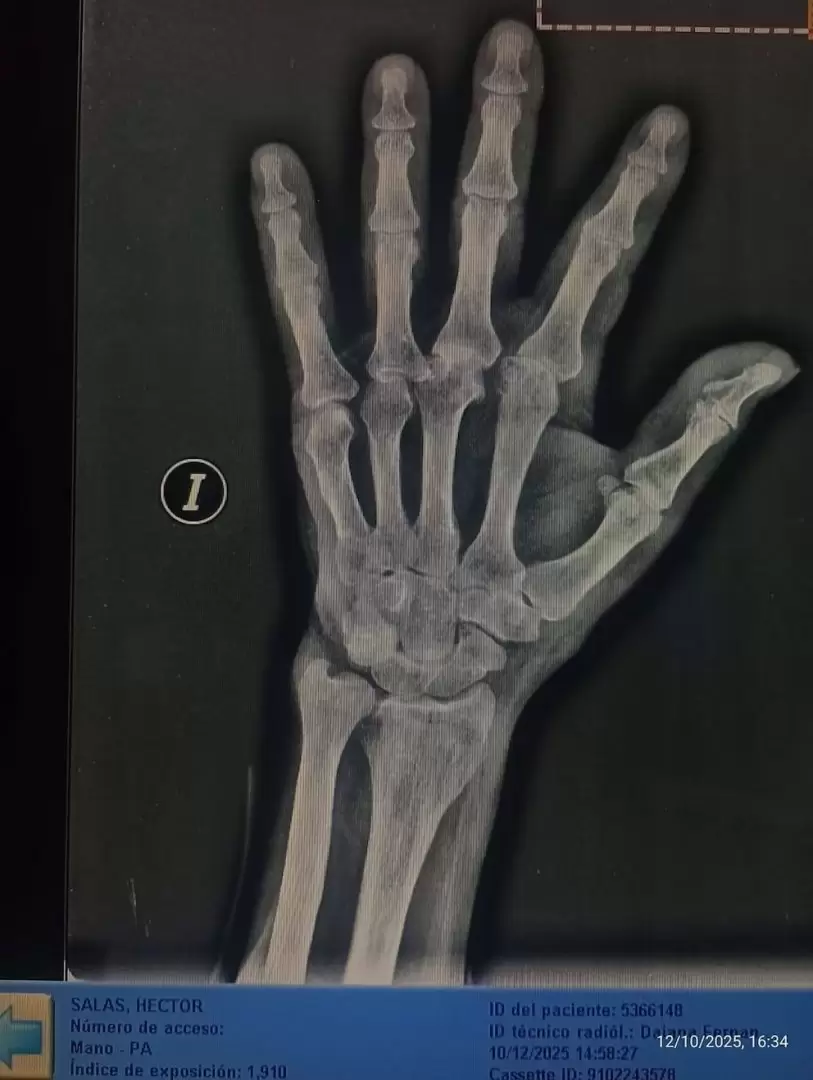

La víctima es Héctor Salas, diagnosticado con Alzheimer. Sus familiares lo encontraron con heridas visibles en el rostro y una fractura en la muñeca. A la gravedad de las lesiones se sumó la viralización del video del ataque, que terminó de desnudar una realidad que hasta entonces permanecía puertas adentro. El episodio ocurrió días atrás en el geriátrico Posada Punta Mogotes, ubicado en General Pacheco al 2000. La fiscal dispuso como primera medida que el hombre fuera retirado del lugar y ordenó una inspección ocular. El resultado fue lapidario: problemas de habilitación, falencias en medidas de seguridad y falta de personal suficiente.

La familia denunció además que la dueña del geriátrico intentó justificar el ataque alegando que Héctor "había sufrido un brote psicótico" tras negarse a tomar una pastilla. La respuesta fue inmediata y contundente: "Le podía haber dado la pastilla disuelta en la comida o en la bebida", acusaron. El diagnóstico médico posterior confirmó fracturas en la mano derecha, especialmente en el dedo pulgar. Pero el daño no fue solo físico. Antes de ser retirado del lugar, el propio Héctor habló en un video que se difundió en redes sociales. "Qué bochinche que se armó, che. Yo vine a pagar sin querer. Se armó la joda y yo también pagué", dijo.